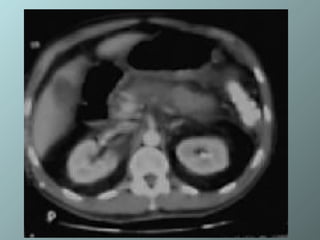

Absceso pancreático: colección heterogenea relativamente bien circunscrita conteniendo burbujas de gas dentro de la cabeza. La colección fue drenada con 1 cateter 12 Fr con cola de chancho

Absceso pancreático: colecciónheterogenea relativamente bien circunscrita conteniendo burbujas de gas dentro de la cabeza. La colección fue drenada con 1 cateter 12 Fr con cola de chancho